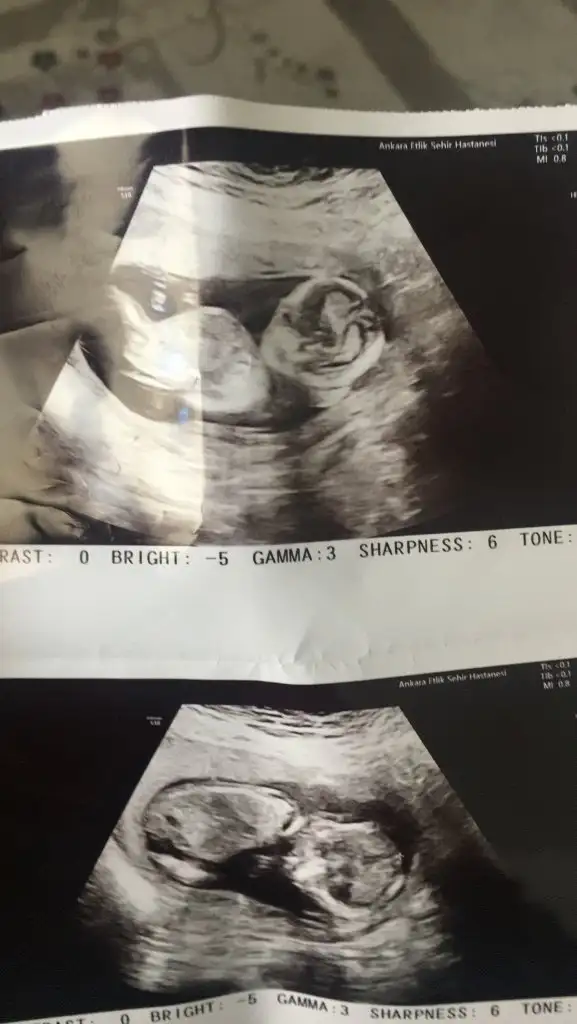

Kızlar normalde 10haftalık acilden geliyorum gaz sıkışmam varmış karın ağrısıyla gittim de cok şükür🤲🏻 Sizce cinsiyetleri nedir